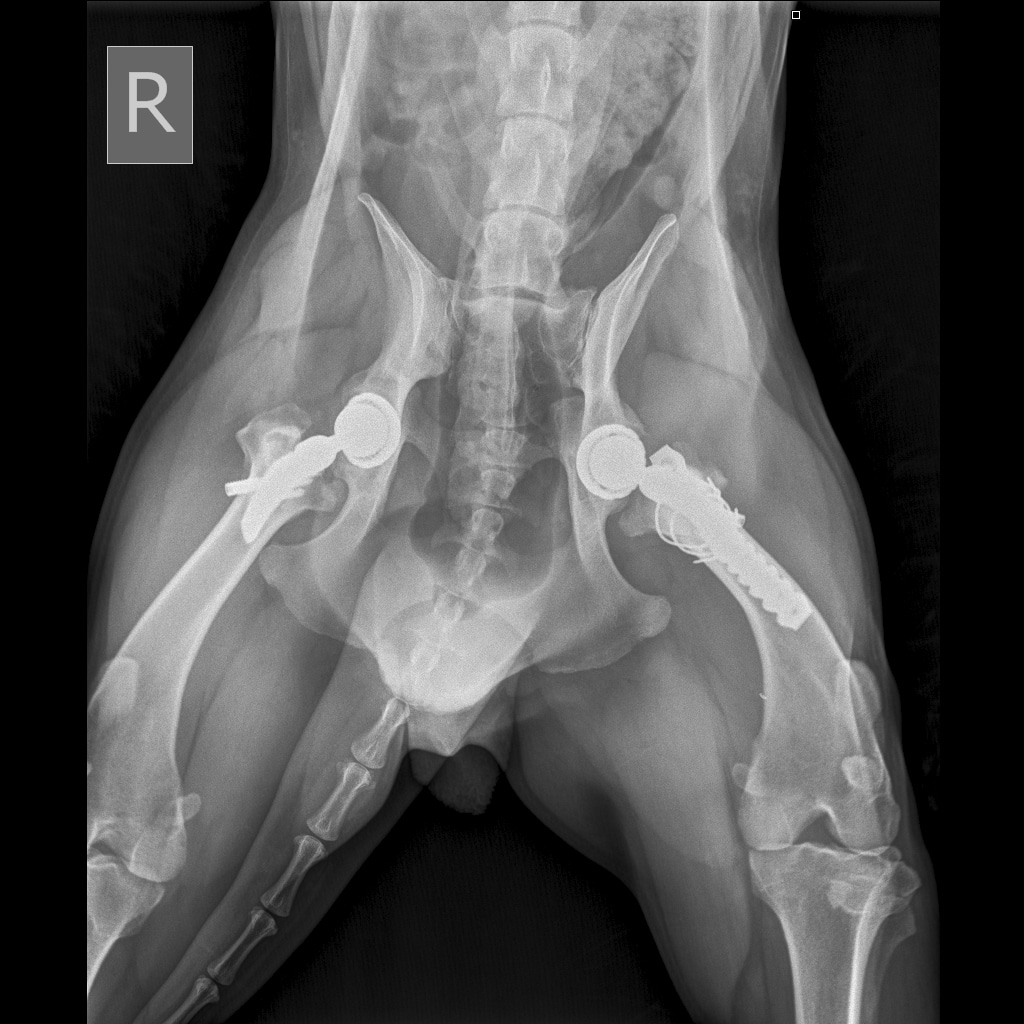

Вчера резко захромал, встал на 3 ноги и понос.

По рентгену чисто